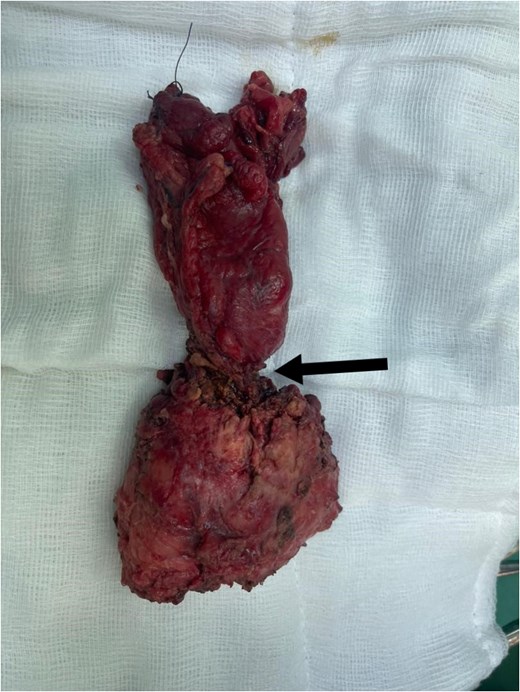

Subsequently, he underwent open low anterior resection with primary colorectal anastomosis, diverting loop ileostomy, and en bloc resection of both ureters. Due to a concurrent urinary tract infection, urinary reconstruction was deferred. The right ureter remained intact, but the left ureter was involved with the tumor and required resection. The resected specimen (Fig. 3) revealed moderately differentiated adenocarcinoma with clear margins, and all six regional lymph nodes were negative for tumor infiltration (pT4a pN0 M0).

Total mesorectal excision (TME) specimen, with arrow pointing to the tumor.